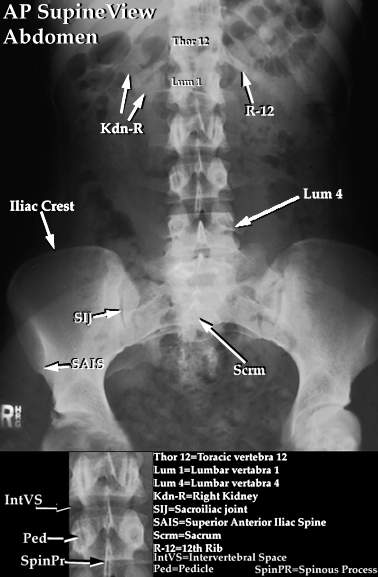

2. NORMAL ABDOMEN

On the plain photo of abdomen, there are several things that should be considered:

2. Soft tissue and visceral out lines of intra abdominal organs

Outlines on soft tissue shows the radiolucent illustration because there is fat layer scoping the intra abdomen organs. Some organs that sometimes can be seen are: hepar, lien, both kidneys (renal outline), maor muscullus psoas and muscullus quadratus lumborum (psoas line).